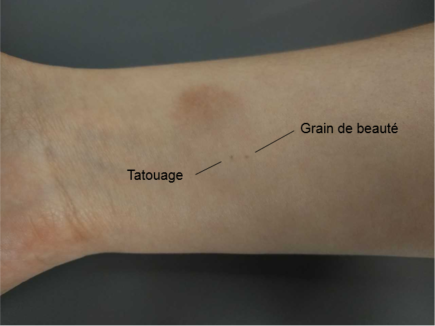

Tatouages

À la fin du scan, un technologue vous fera quelques points permanents de taille minime (1-2 mm) à l’aide d’une petite aiguille. Ces tatouages permettront aux technologues en salle de traitement de vous positionner correctement chaque jour. Vous pouvez vous laver normalement, les tatouages ne disparaîtront pas.